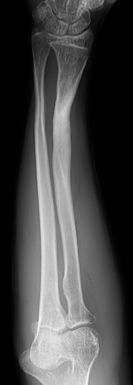

2. Fracturas de antebrazo

Las fracturas de antebrazo constituyen aproximadamente el 45% de todas las fracturas en la infancia y el 62% de las fracturas de la extremidad superior. El tratamiento de las fracturas de antebrazo ha variado de forma considerable en los últimos años. Hasta finales de los años 80, la mayoría se trataban de forma conservadora con malos resultados funcionales debido a consolidaciones viciosas. Posteriormente, la utilización de clavos intramedulares elásticos permitió un tratamiento definitivo de una forma poco invasiva.

El tratamiento de las fracturas de antebrazo dependerá del grado de desplazamiento y localización.

A. Fracturas del tercio distal del radio y cúbito (75-85%):

Son las más frecuentes en la infancia. La capacidad de remodelación es máxima en niños pequeños, menores de 8 años, cuando el trazo de fractura está cercano a la fisis y en el plano de movimiento de la articulación.

Las fracturas no desplazadas o mínimamente desplazadas, menos de 30° de angulación dorsal y menos de 20° desviación radial, en niños menores de 8 años pueden tratarse de forma conservadora con buenos resultados con un yeso bien moldeado con tres puntos de apoyo para evitar el desplazamiento secundario.

Las fracturas desplazadas o inestables precisarán de reducción cerrada o abierta en quirófano, asociado en algunos casos a osteosíntesis (Figura 10). Las fracturas localizadas en la unión metafiso-diafisaria distal son inestables y en muchos caos requieren tratamiento quirúrgico (Figura 11).